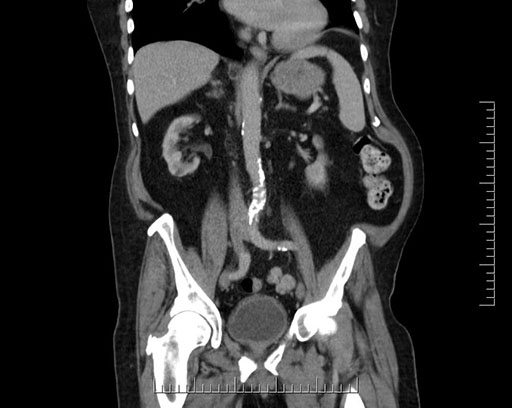

Coronal - stented